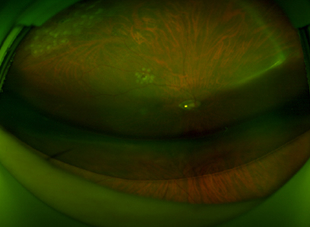

수술 전 사진

Before Surgery

수술 후 2일 사진

2 Days Post-Op

(Air 80%)

수술 후 7일 사진

7 Days Post-Op

(Air 30%)

수술 후 10일 사진

10 Days Post-Op

(Air 0%)